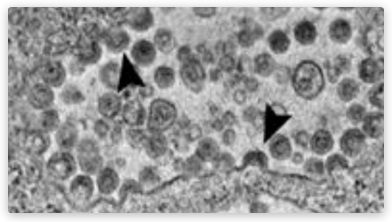

GESUNDE Blutzellen -

und GENgeimpfte Blutzellen: Letztere sind

verknittert und teilweise schon verklumpt,

Thrombosen kündigen sich an

GESUNDE Blutzellen - und GENgeimpfte Blutzellen: Letztere sind verknittert und teilweise schon verklumpt, Thrombosen kündigen sich an

Video-Link: https://brandnewtube.com/watch/discovery-what-covid-injections-do-to-your-blood-dr-releases-horrific-findings_m1kR5B4RfZwfKCA.html